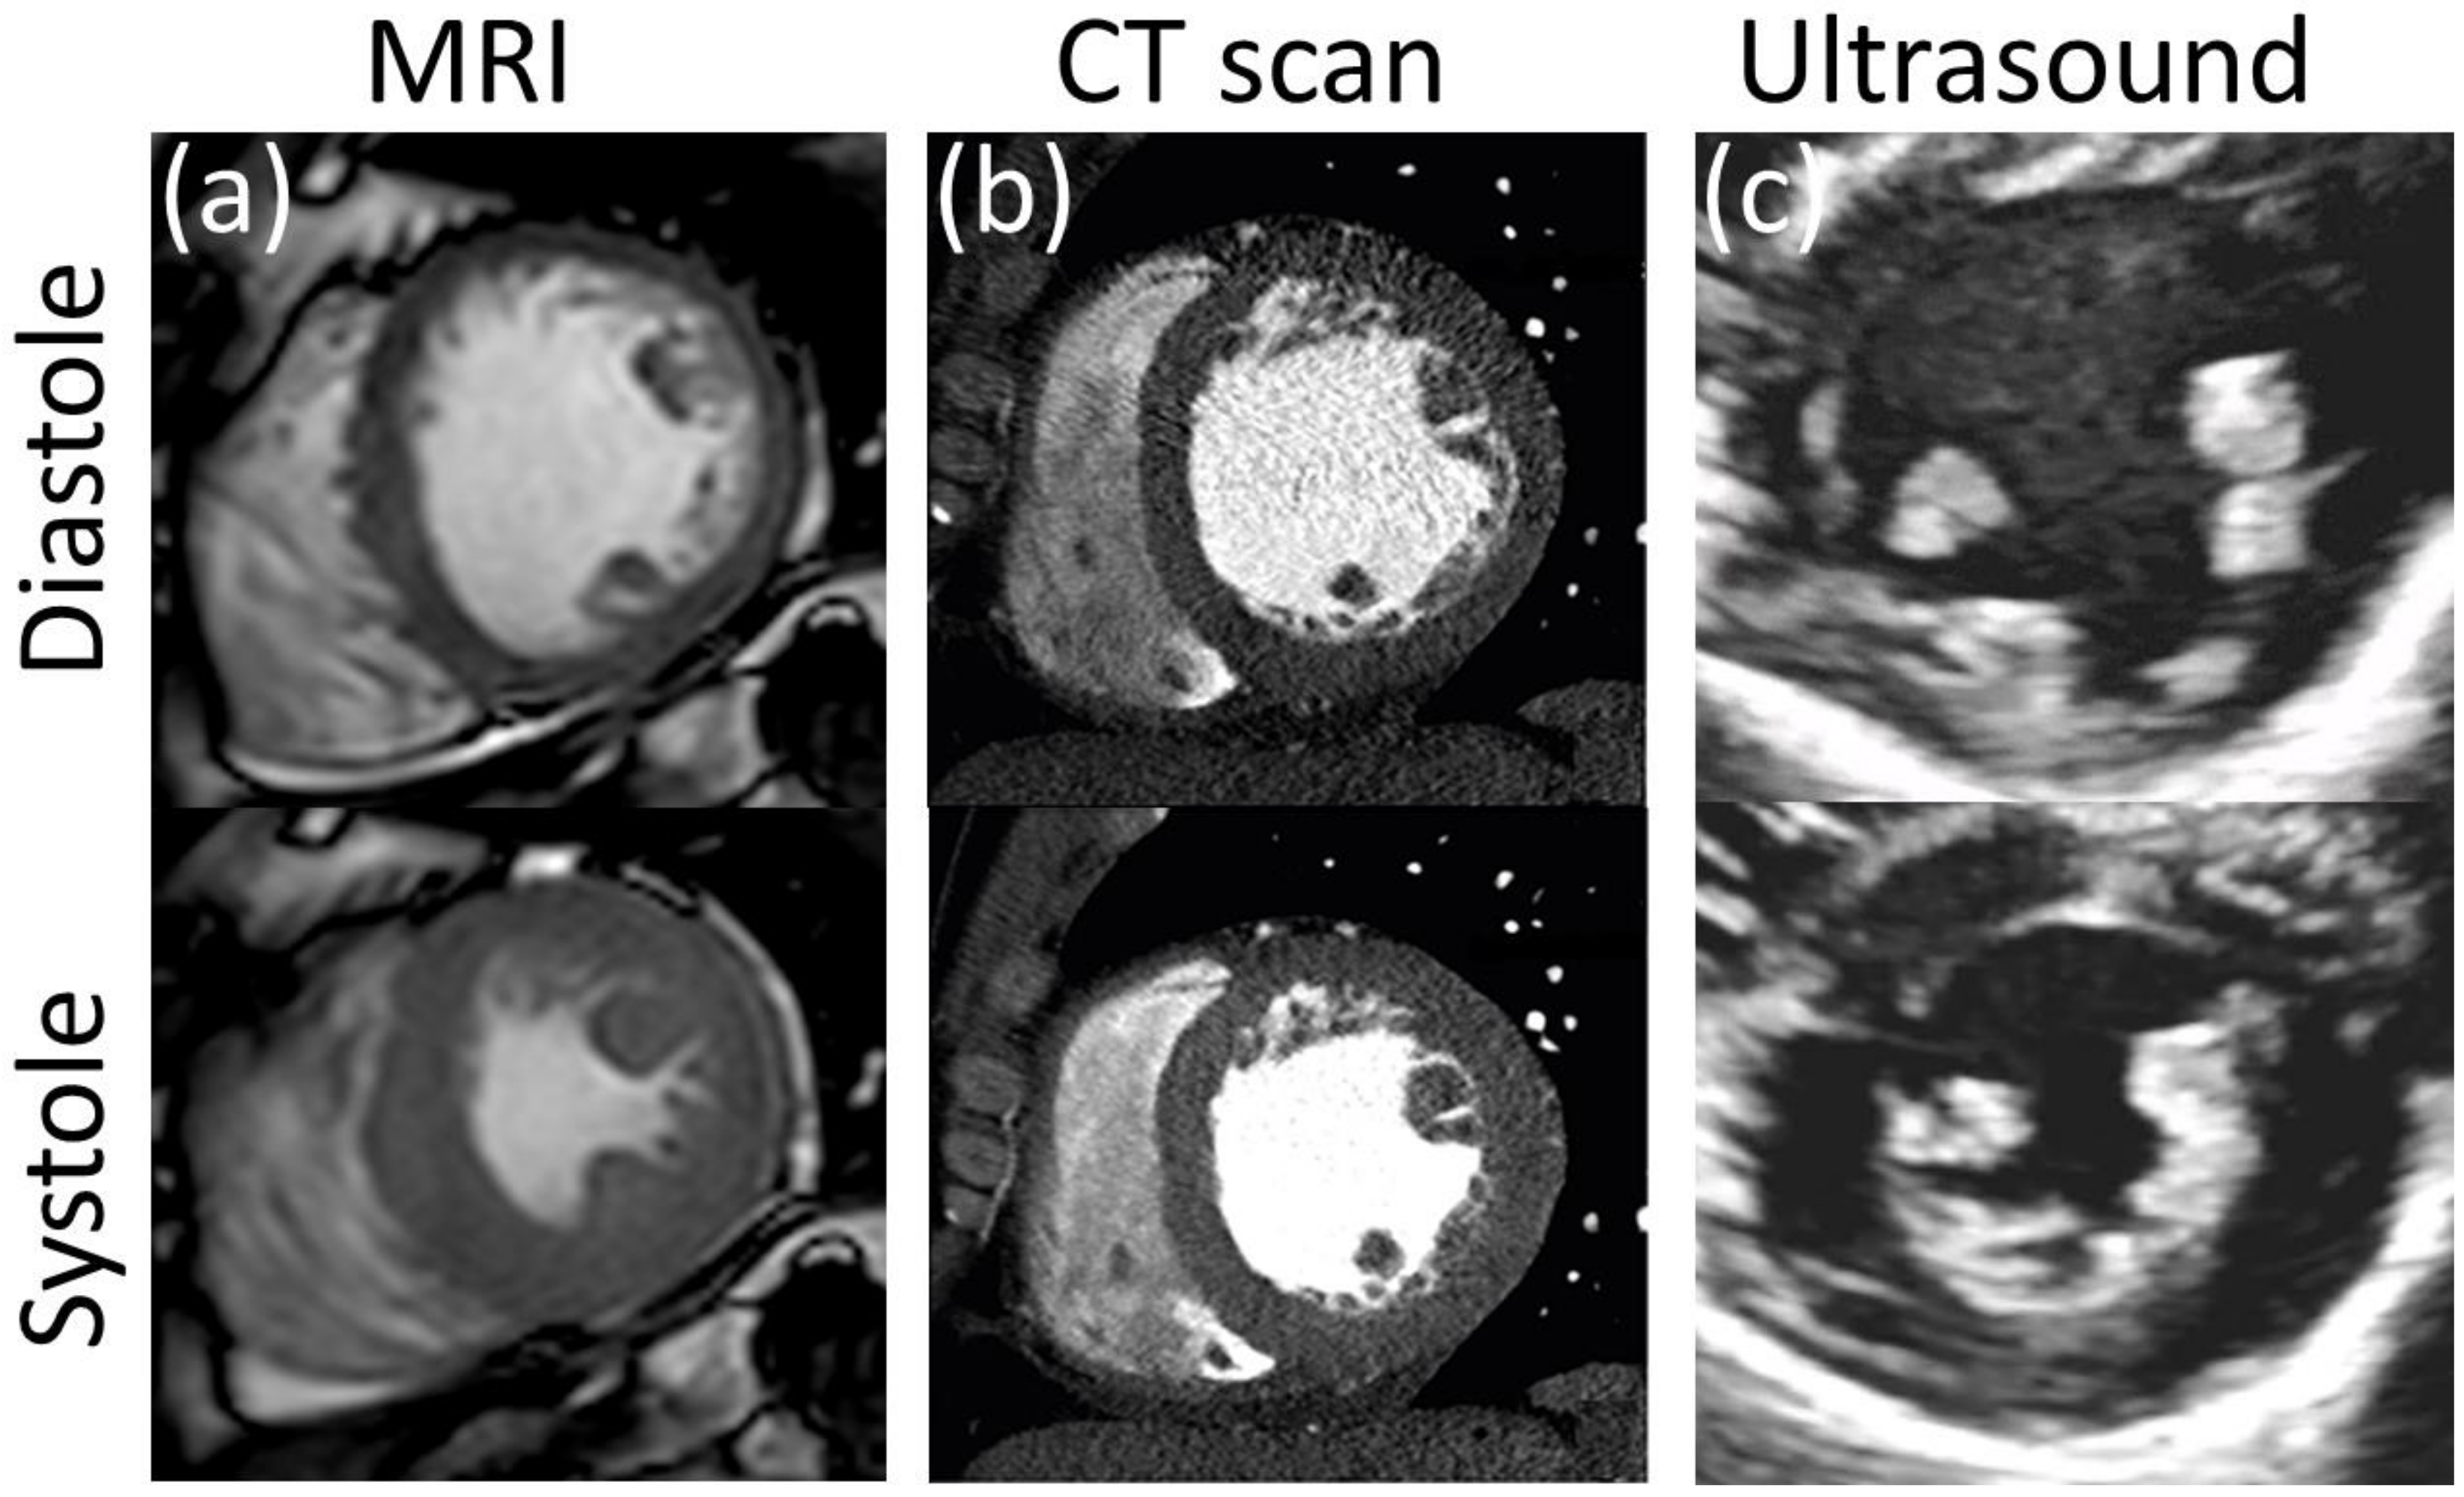

Ultrasound (US) uses high frequency (2 to 15 MHz) acoustic waves to create real-time 2D in vivo images of tissues, organs, and blood pools using piezoelectric transducers. As in any wave, higher frequencies are associated with smaller wavelengths, higher penetration power, and improved image resolution [152,153]. Volume rendering from ultrasound images has led to three-dimensional, time-resolved ultrasound (4D US), and real-time imaging [154]. US is relatively inexpensive, portable, and safe, so it has become a customary tool in many clinical applications such as anesthesia, critical care, prenatal care, and pain management. Its application to cardiology, commonly known as echocardiography, was introduced in the 1950s, and currently is the more ubiquitous diagnostic tool to assess cardiovascular structure and function. With an approximate lateral resolution of 1 mm/pixel, this technique allows the estimation of heart chamber size, valve structure, identification of structural abnormalities such as seen in congenital heart defects (CHD), and determination of systolic and diastolic function (Figure 7c) [155]. Nevertheless, echocardiography presents some intrinsic limitations regarding accuracy and repeatability, particularly in patients with complex flow patterns related to congenital heart disease, aortic regurgitation, or dissection, in which case it is recommended to complement the study with other imaging techniques [156]. Intravascular ultrasound technology (IVUS) was developed following the principle that accuracy and resolution are improved as the transducer is closer to the tissue of interest. This technology involves placing a miniature ultrasound probe at the end of a catheter and then introducing the catheter into the vessel of interest in order to resolve the surrounding structures with greater detail than allowed by standard external US. This invasive technique is mostly used to study the conditions and progression of atherosclerosis in patients with coronary and carotid artery disease [157]. US technology can also provide blood flow and tissue kinematic information through the use of echo-Doppler and speckle tracking techniques.

Figure 7.

Resolution comparison of left ventricular myocardium at diastole and systole with clinical grade (a) MRI, (b) CT (Reprinted/adapted with permission from Ref. [158], 2019, Korean Society of Echocardiography, open access), and (c) 2D ultrasound.